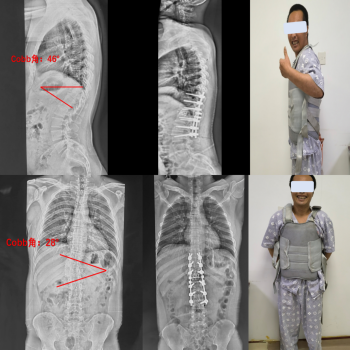

术前全脊柱全长X线正侧位示:胸椎后凸Cobb角46°;侧凸Cobb角28°;CT三维重建示:胸11、胸12蝴蝶椎异常发育

手术后第4天,小陈已经可以佩戴腰椎支具独自站立行走了。望着镜子中胸背挺拔的自己,终于绽开了自信的微笑,自言自语道:“爸爸,你看我好像长高了2厘米!”

术前术后全脊柱正侧位X线